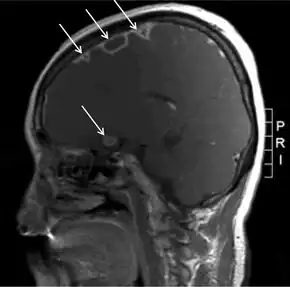

During the primary infection, F. necrophorum colonizes the infection site and the infection spreads to the parapharyngeal space. The bacteria then invade the peritonsillar blood vessels where they can spread to the internal jugular vein.[6] In this vein, the bacteria cause the formation of a thrombus containing these bacteria. Furthermore, the internal jugular vein becomes inflamed. This septic thrombophlebitis can give rise to septic microemboli[12] that disseminate to other parts of the body where they can form abscesses and septic infarctions. The first capillaries that the emboli encounter where they can nestle themselves are the pulmonary capillaries. As a consequence, the most frequently involved site of septic metastases are the lungs, followed by the joints (knee, hip, sternoclavicular joint, shoulder and elbow[13]). In the lungs, the bacteria cause abscesses, nodulary and cavitary lesions. Pleural effusion is often present.[7] Other sites involved in septic metastasis and abscess formation are the muscles and soft tissues, liver, spleen, kidneys and nervous system (intracranial abscesses, meningitis).[6]